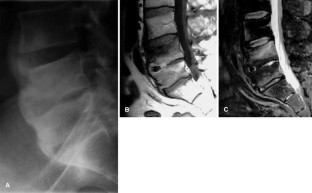

Fig. 3.